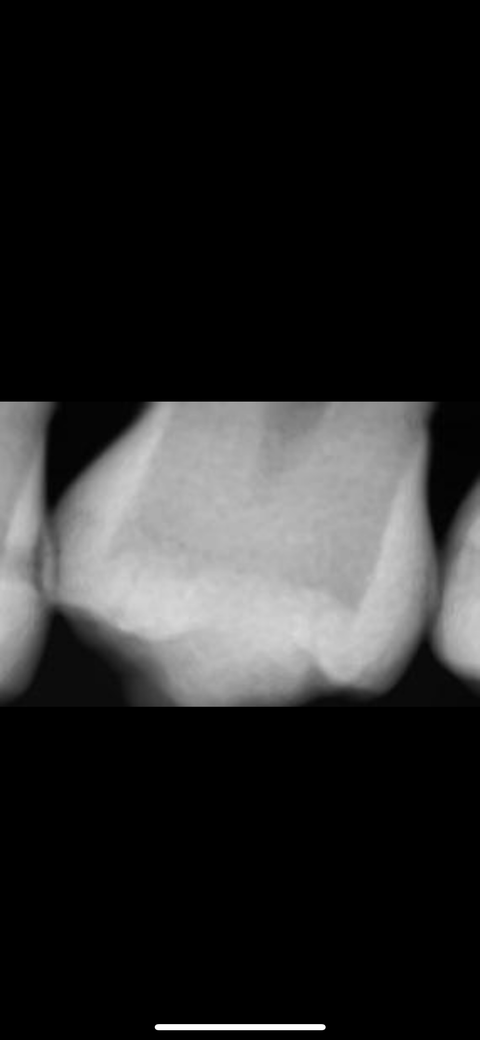

한색 하고 약간 누룽지 갈색 충치인가요 변색인가요?

저 부분을 충치치료해야한다 하셨는데 교익사진에는 전혀 깊어보이지가 않거든요 교익이 더 정확하지않나요? 그리고 저부분은 인레이를 해야되는 위치인거같은데요

방사선 사진상에서는 충치의 소인이 보이고 있긴 합니다 하지만 충치의 정도는 육안으로 확인을 해야 하는 것이기 때문에 육안을 확인을 해서 충치를 치료할 필요가 있다면 충치를 치료해 주는 것이 좋습니다.

교익사진을 보면 치아 사이에 충치가 잇는거 같습니다. 인접면에 충치가 잇으면 레진 또는 인레이 치료를 하시면될것같습니다.